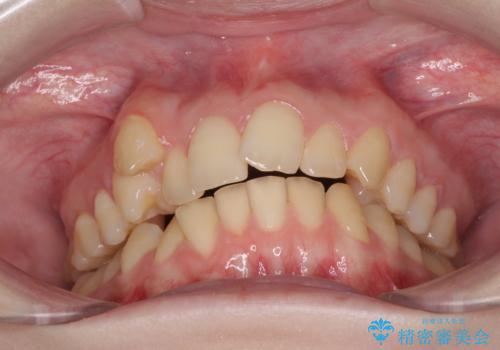

- 著しい八重歯を気にして来院された患者様です。

片側の八重歯であり上顎の正中がずれていたため、上顎左右第一小臼歯2本を抜歯して排列することとしました。

下顎の骨格的なズレが大きかったため、上下歯列のバランスが取れるか心配でしたが、上下ともに左右対称に近い歯列で治療を終えることができました。